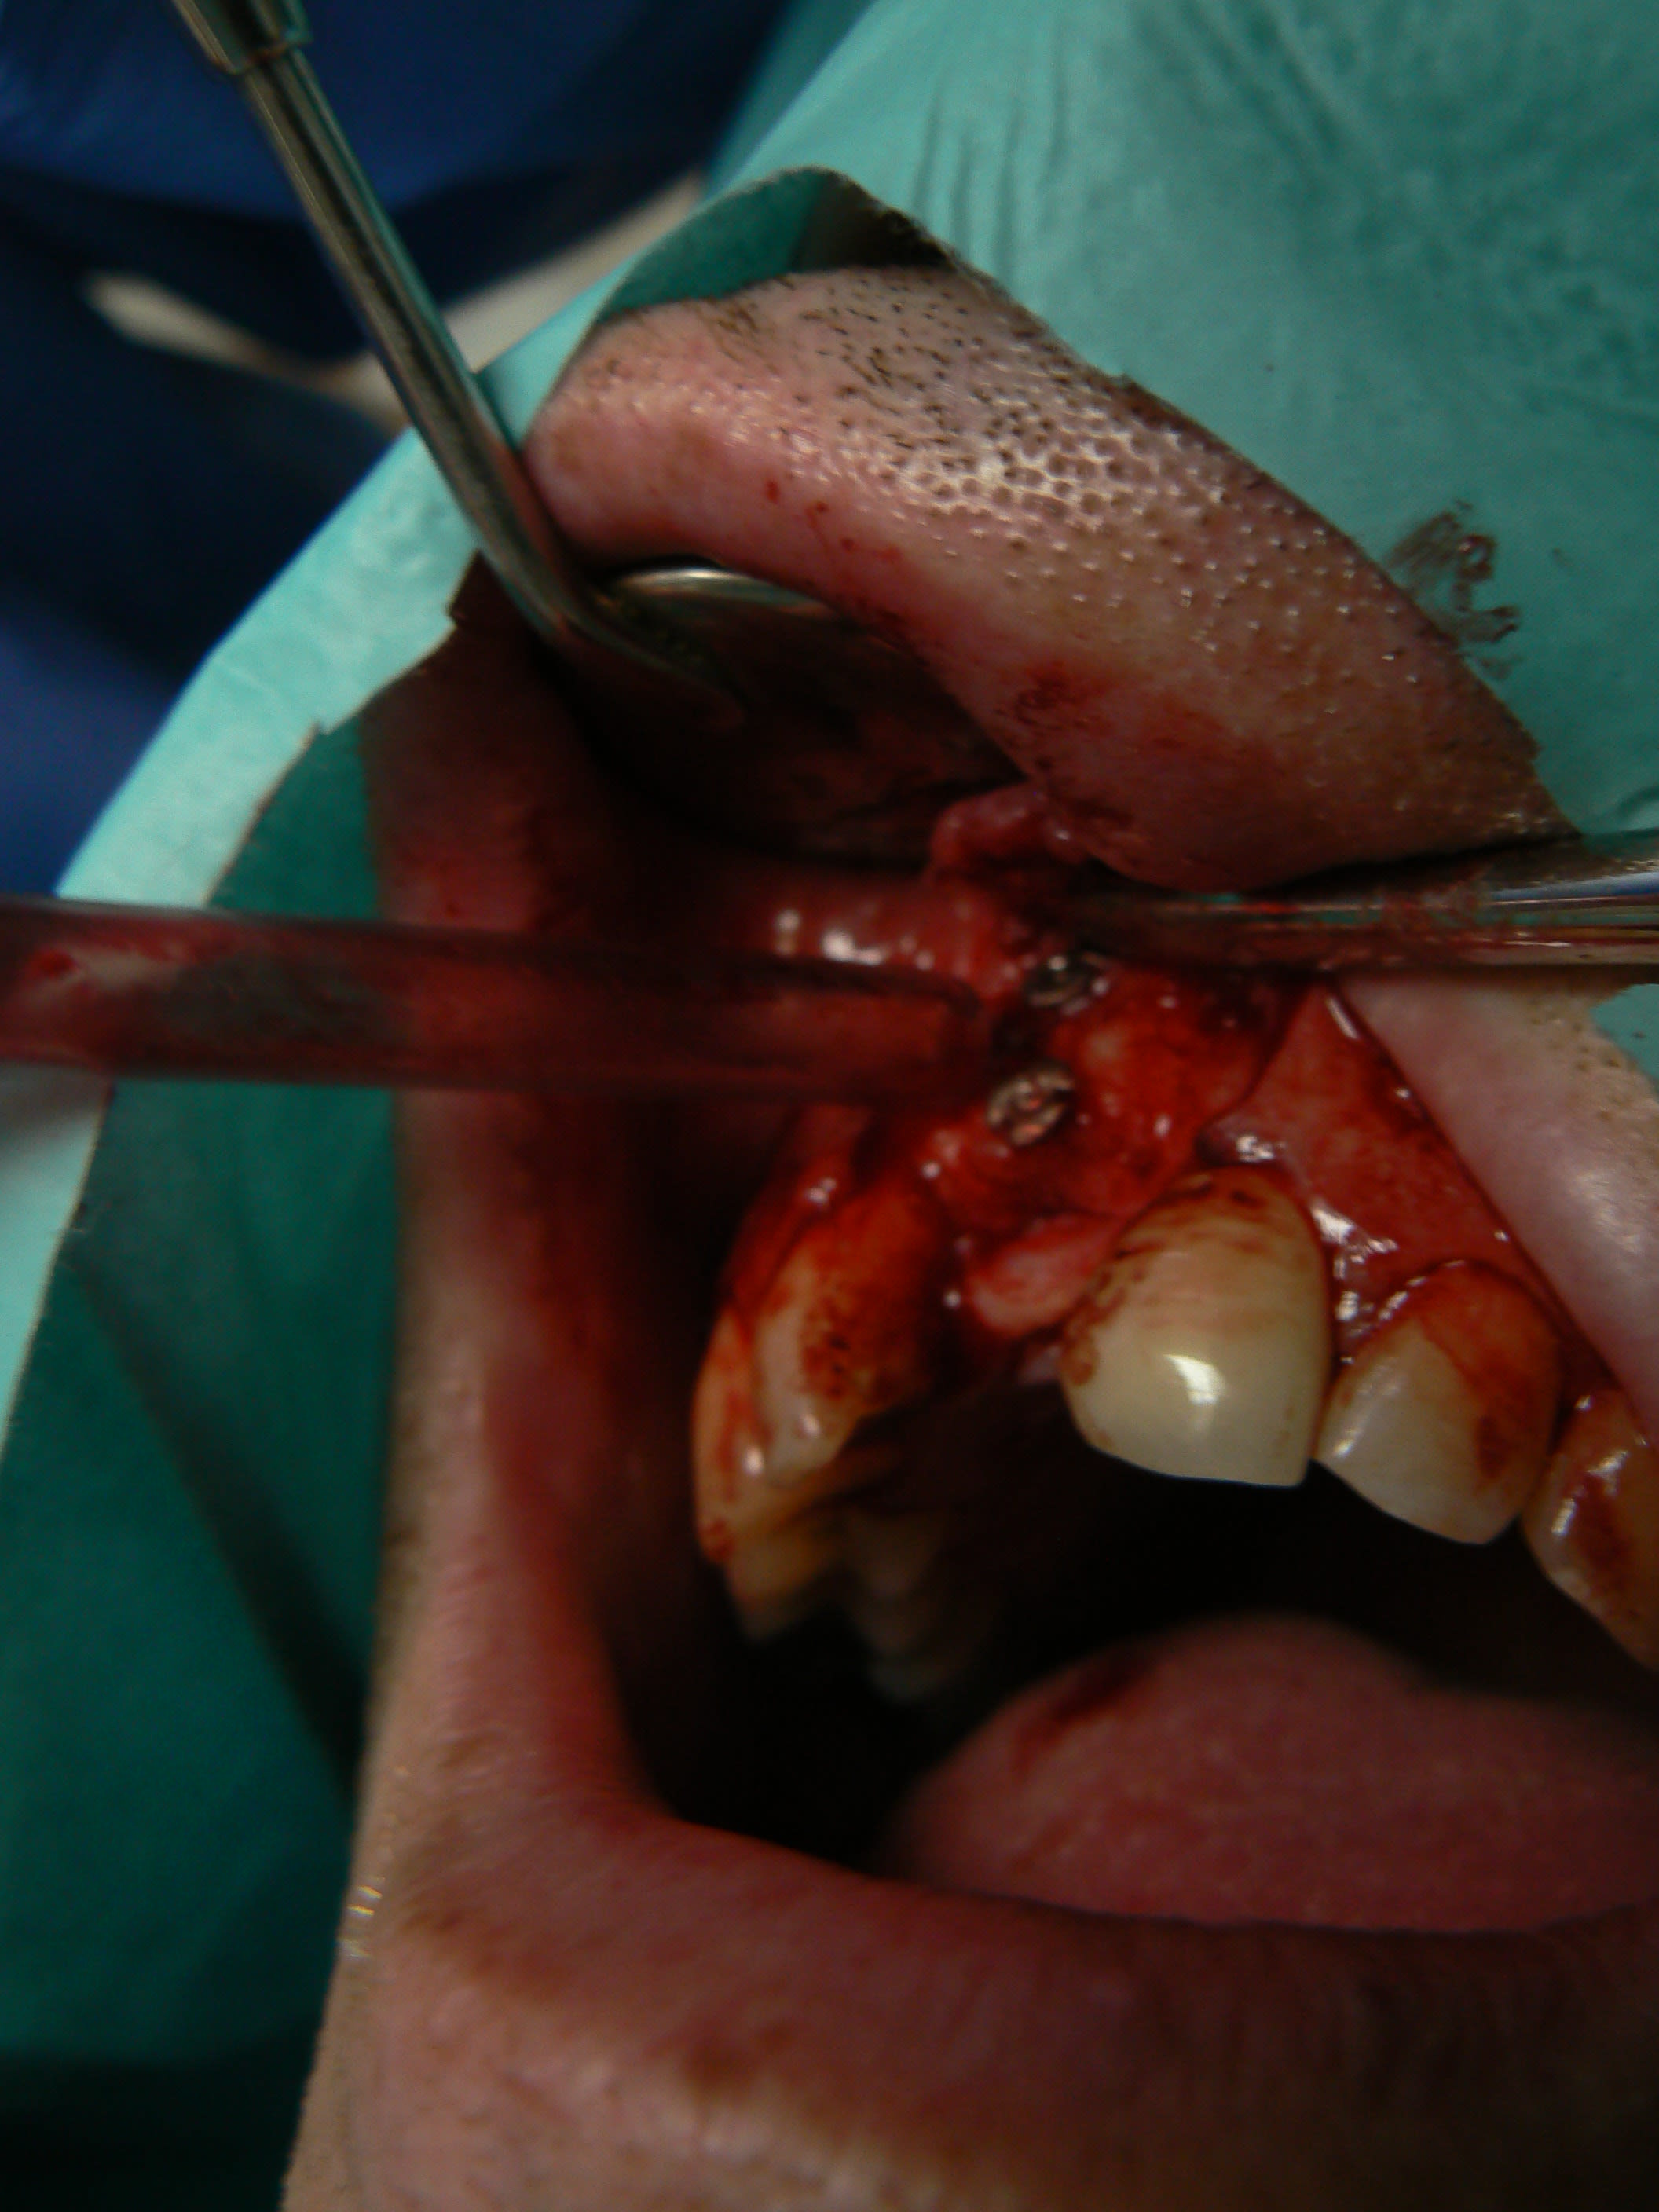

> Ci joint cas avec biobank, très bonne stabilité et consistance a la réouverture

> a 9 mois.

j'ai retrouvé, mais c'est le correspondant qui à posé l'implant et les photos sont pas top :(

j'essaie d'envoyer si ça marche

ceux sont les photos du correspondant .